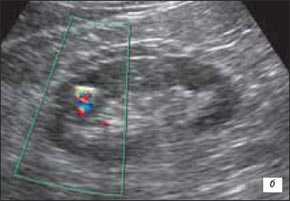

• Цветовая допплерография:

о Нормальная перфузия указывает на неизмененную почечную ткань

о Отсутствует деформация сосудов с нормальными дугообразными артериями, окружающими пирамиды

о Отсутствуют аномальные сосуды

(Левый) Продольный ультразвуковой срез правой почки, визуализируется гипертрофирован ная бертиниева колонна, изоэхогенная корковому веществу почки.

(Правый) МРТ с контрастным усилением у этого же пациента (по поводу другого заболевания почки; не показано), визуализируется очаг такой же интенсивности сигнала, как и корковое вещество почки, сравнимое с гипертрофированной бертиниевой колонной.